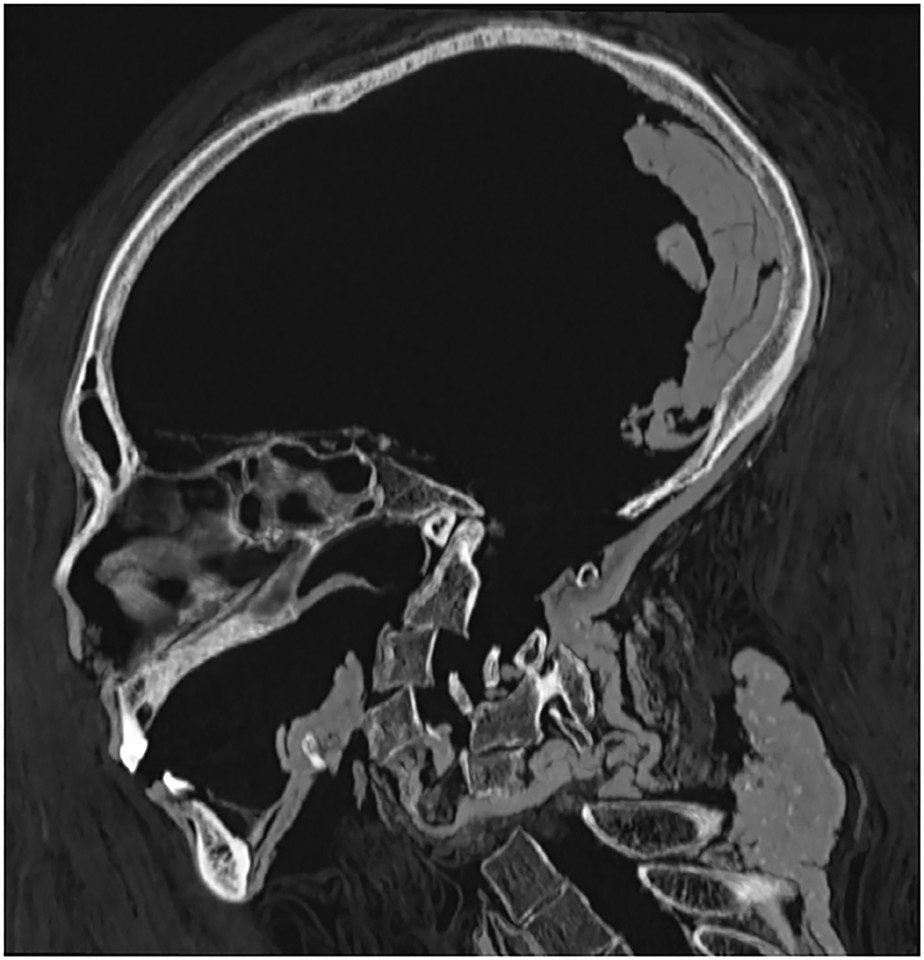

Computed tomography (CT) technology, which creates a cross-section of a body using X-rays, revealed the pharaoh’s face and a chest full of treasure, including 30 amulets and “a unique golden girdle with gold beads,” study co-author Sahar Saleem said in a statement. The findings were published Tuesday in the journal Frontiers in Medicine.

“By digitally unwrapping the mummy and ‘peeling off’ [the layers around the body] — the face mask, the bandages and the mummy itself — we could study this well-preserved pharaoh in unprecedented detail,” Saleem, a radiology professor at Cairo University’s school of medicine, added.

Mystery remains concerning the death of Amenhotep. CT scans revealed no “wounds or disfigurement due to disease to justify the cause of death,” said Saleem, who found “numerous mutilations post mortem, presumably by grave robbers after his first burial.”

His brain was also undisturbed — perhaps one of the few remaining royals during Late Period ancient Egypt to have kept it, as the process of removing the brain, bit-by-bit through the nose, was popularized around 3,500 years ago. He also died with a healthy set of teeth, and was evidently circumcised, as was tradition.

He “seems to have physically resembled his father,” Ahmose I, according to Saleem. “He had a narrow chin, a small narrow nose, curly hair and mildly protruding upper teeth.”